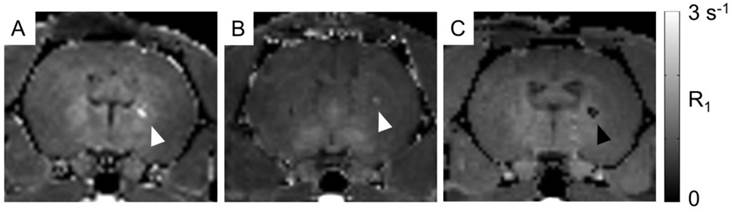

For proof of concept in vivo cell detection with MRI, three rats were transplanted with hNPC-DMT1 in the right striatum and hNPC-WT in the left. Two days later, MnCl2 was delivered systemically in preparation for MR imaging. At 48 and 72 hours later, the animals were imaged with a T1 mapping sequence to observe the T1 shortening effects of Mn2+. After imaging and perfusion, histological evaluation was performed to verify cell survival through the transplantation and imaging procedure. In two of the three MRI subjects, a region of increased R1 was observed in the right striatum (Figure 7). This contrast corresponds to the location of transplanted hNPC-DMT1, detected histologically with antibodies against human GFAP (used to detect human cells) and human DMT1 (Figure 8). Wild-type cells transplanted contralaterally were also detected histologically, ruling out the possibility that hNPC-WT were undetectable in MRI simply due to cell death. These preliminary in vivo results, along with the Mn2+ uptake measured in vitro, strongly support our hypothesis that high levels of manganese are taken up in DMT1 over-expressing hNPC, permitting in vivo visualization with MRI.

However, in one of the three subjects, a decrease in R1 was observed in the vicinity of hNPC-DMT1 (Figure 7C). In this same region, T2-weighted imaging showed a hypointense region corresponding to cell location (Supplementary Material: Figure S1A). This is likely due to surgery-induced hemorrhage in the brain, which we have found to be a challenging confounding factor in MRI of transplanted hNPC. Iron accumulation was detected with Prussian blue staining and could wipe out MR signal, making T1 calculation impossible (Supplementary Material: Figure S1B).

Figure 7

In vivo manganese-enhanced MRI of rats after hNPC-DMT1 transplantation. (A and B) In two of three subjects, hNPC-DMT1 were detectable on R1 maps (white arrowheads). (C) In one subject, T1 mapping failed in the vicinity of hNPC-DMT1, possibly due to hemorrhage-related iron accumulation (black arrowhead).